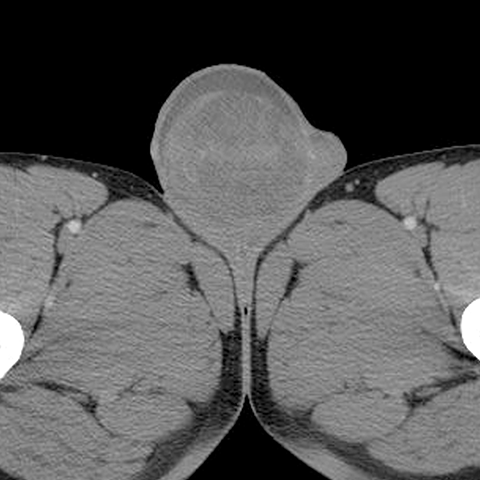

Mixed germ cell tumor [1 of 2]